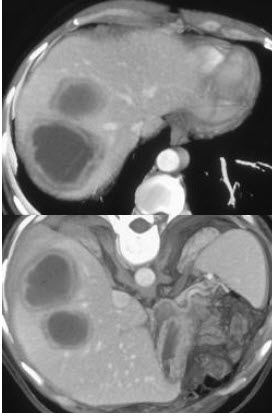

56、单项选择题

下列图像的最佳诊断是()

A.阿米巴肝脓肿

B.原发性肝癌

C.肝硬化

D.脂肪肝

E.肝囊肿